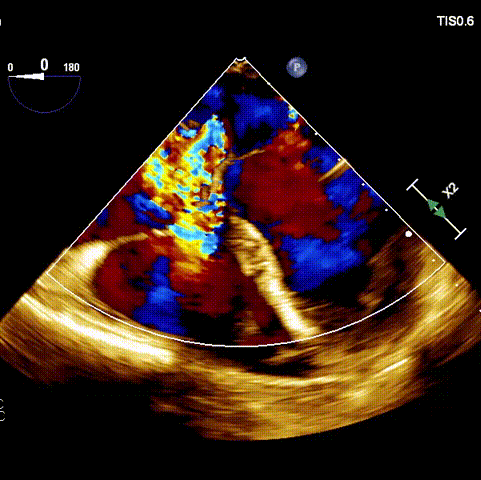

術(shù)前超聲

術(shù)前經(jīng)過(guò)全面系統(tǒng)的評(píng)估后,考慮患者存在高齡、心功能減低、三尖瓣瓣環(huán)重度擴(kuò)張(三尖瓣極重度反流)等高危因素,因此廈心結(jié)構(gòu)心團(tuán)隊(duì)聯(lián)合超聲心動(dòng)、麻醉及護(hù)理團(tuán)隊(duì),制定了詳盡的圍術(shù)期治療方案及術(shù)中治療難點(diǎn)預(yù)案。術(shù)中,由王焱院長(zhǎng)主刀,在蘇茂龍主任超聲心動(dòng)團(tuán)隊(duì)的輔助,上海市第一人民醫(yī)院陸方林主任的協(xié)助下,僅用時(shí)30分鐘,即順利完成了三尖瓣原位置換的手術(shù)。術(shù)中患者血流動(dòng)力學(xué)穩(wěn)定,術(shù)后即刻顯示LuX-Valve Plus瓣膜位置良好,固定穩(wěn)定,瓣膜功能正常,無(wú)瓣周漏。

術(shù)后超聲